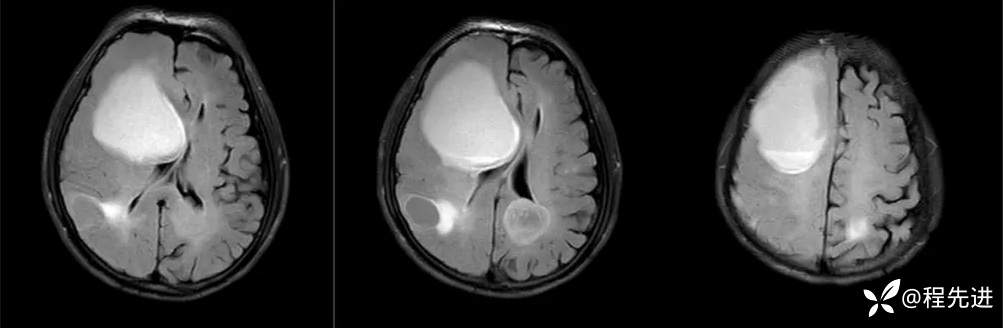

FLAIR: